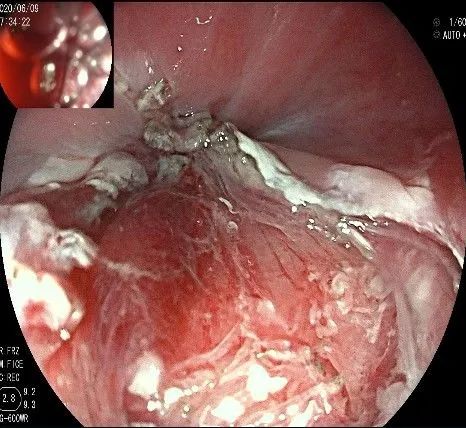

再次进镜观察,齿状线炎性息肉的地方,用圈套器圈套后通电切除。

瘤子切除后,在粘膜切开的地方,固有肌层的纵形肌处形成一个开口。

倒镜观察,隆起已经消失。

夹闭创面的时候做胃镜吸引,利于创面闭合。

创面夹闭完成,反复冲洗观察,无出血及穿孔。结束手术,等待病理结果。